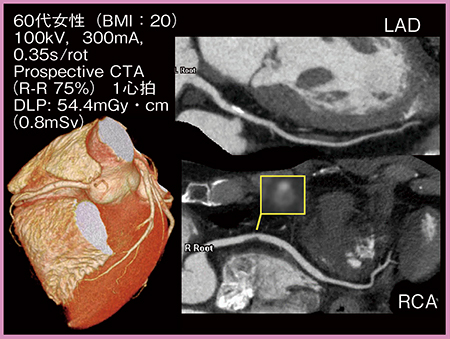

症例1は,DLP 54.4mGy・cm,実効線量0.8mSvと,1mSv以下の被ばく線量で冠動脈の非石灰化プラークが明瞭に描出されており,ナプキンリングサインと思われるハイリスクプラークの同定も可能であった(図1)。

図1 症例1:低被ばく撮影における非石灰化プラークの描出